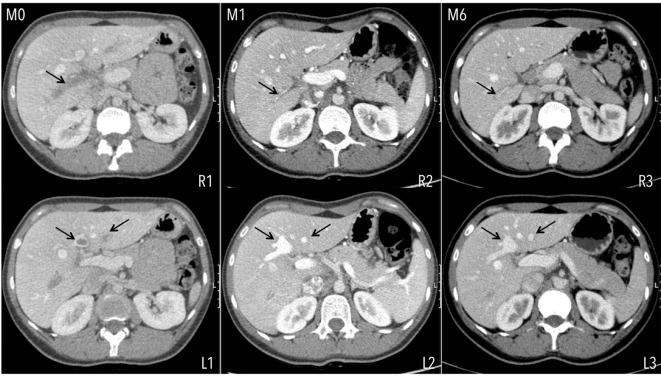

In acute portal vein thrombosis (APVT) unrelated to cirrhosis, anticoagulant therapy is classically started with low molecular weight heparin or vitamin K antagonists. New direct-acting oral anticoagulants (DOACs) are used in the treatment of venous thrombosis outside the splanchnic vascular bed, but not in the latter. We report a young female with APVT occurring in a non-cirrhotic liver linked to heterozygosity of factor V-Leiden and prothrombin G20210A gene mutations. Rivaroxaban was started, with total recanalization of the left and partial recanalization of the right portal vein branches, without complications. New DOACs do not need daily subcutaneous injections nor routinely blood coagulation control tests, making its use attractive, eventually increasing patient's compliance. If proved to be safe and effective in the future studies, its use may be extended to PVT treatment. This case shows that rivaroxaban was safe, not only prevented the extension of thrombosis in the portal tract, but also resolved PVT, at least partially.

在与肝硬化无关的急性门静脉血栓形成(APVT)中,抗凝治疗传统上始于低分子量肝素或维生素K拮抗剂。新型直接作用口服抗凝剂(DOACs)用于治疗内脏血管床以外的静脉血栓形成,但不适用于后者。我们报告了一名年轻女性,其APVT发生在非肝硬化肝脏中,与因子V莱顿和凝血酶原G20210A基因突变的杂合性有关。开始使用利伐沙班治疗,左门静脉完全再通,右门静脉分支部分再通,且无并发症。新型DOACs无需每日皮下注射,也无需常规进行凝血控制测试,这使其使用具有吸引力,最终提高了患者的依从性。如果在未来研究中被证明安全有效,其应用可能会扩展到门静脉血栓形成(PVT)的治疗。该病例表明,利伐沙班是安全的,不仅防止了门静脉血栓在门静脉区域的扩展,还至少部分地溶解了PVT。